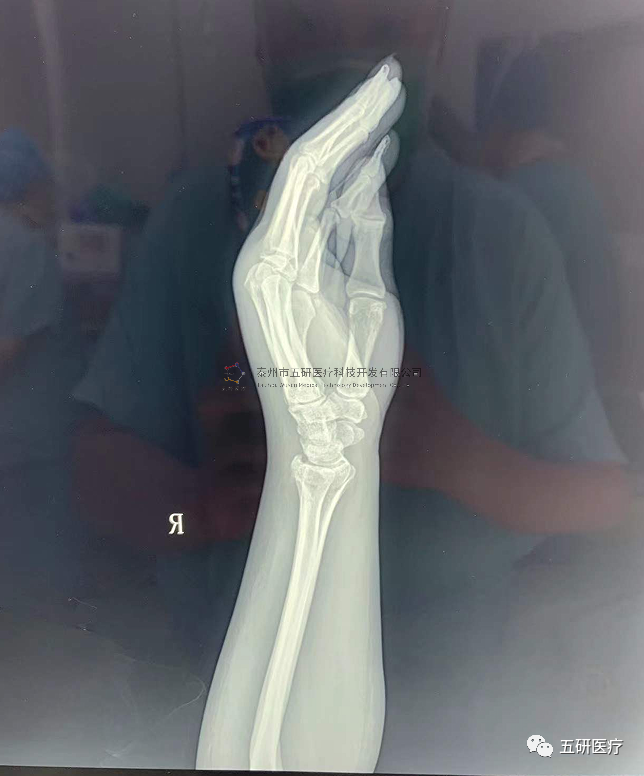

// 腕架

本病例由中國中醫(yī)科學(xué)院望京醫(yī)院骨綜科提供(術(shù)者:支架醫(yī)生常醫(yī)師)

【基本資料】患者,女,61歲

本病例腕架骨折。術(shù)前正側(cè)位片:右橈骨遠(yuǎn)端骨折。

采用常規(guī)方法固定,自掌骨尺側(cè),約基底稍偏遠(yuǎn)處穿入螺紋針。

外架馬蹄環(huán)穿過骨針,更方便調(diào)整固定角度。